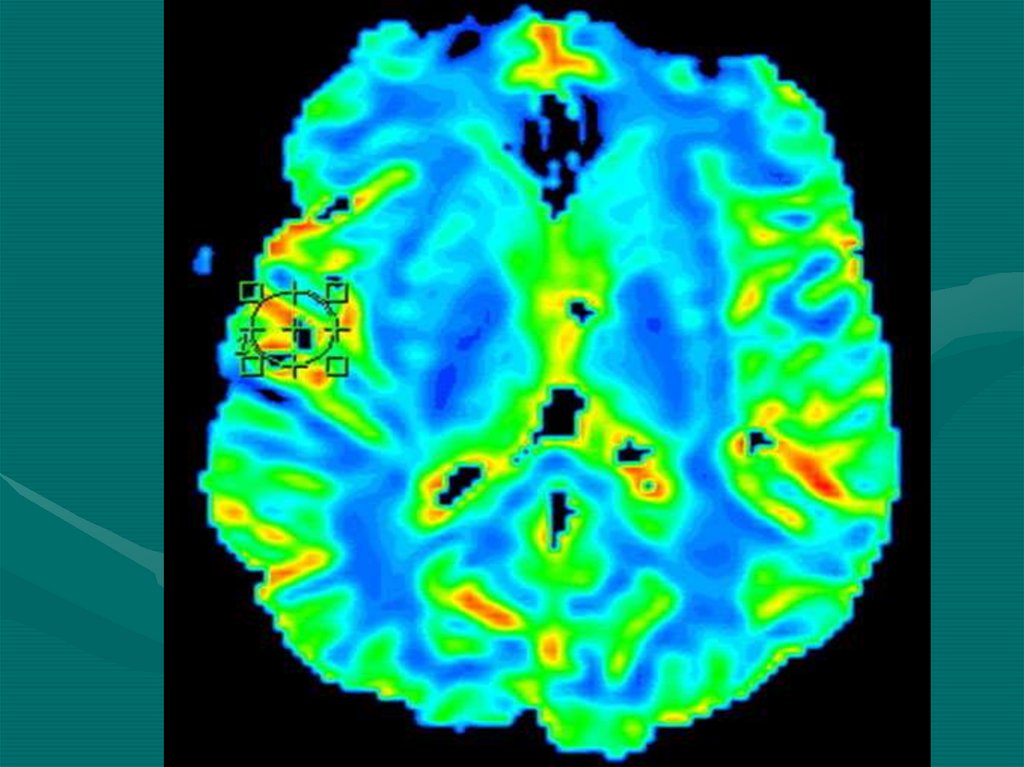

12. ЯМР-резонансная группа

• МРТ (Магнитно-резонансная томография)

• МРС (Магнитно-резонансная спектроскопия)

• Позитронно-эмиссионная томография

• Энцефалосцинтиграфия

• Энцефалоангиосцинтиграфия

13.

14.

15.

16. Нейровизуализация

Совокупность

функциональных явлений и

технологических методов,

создающая прижизненное

изображение ЦНС.